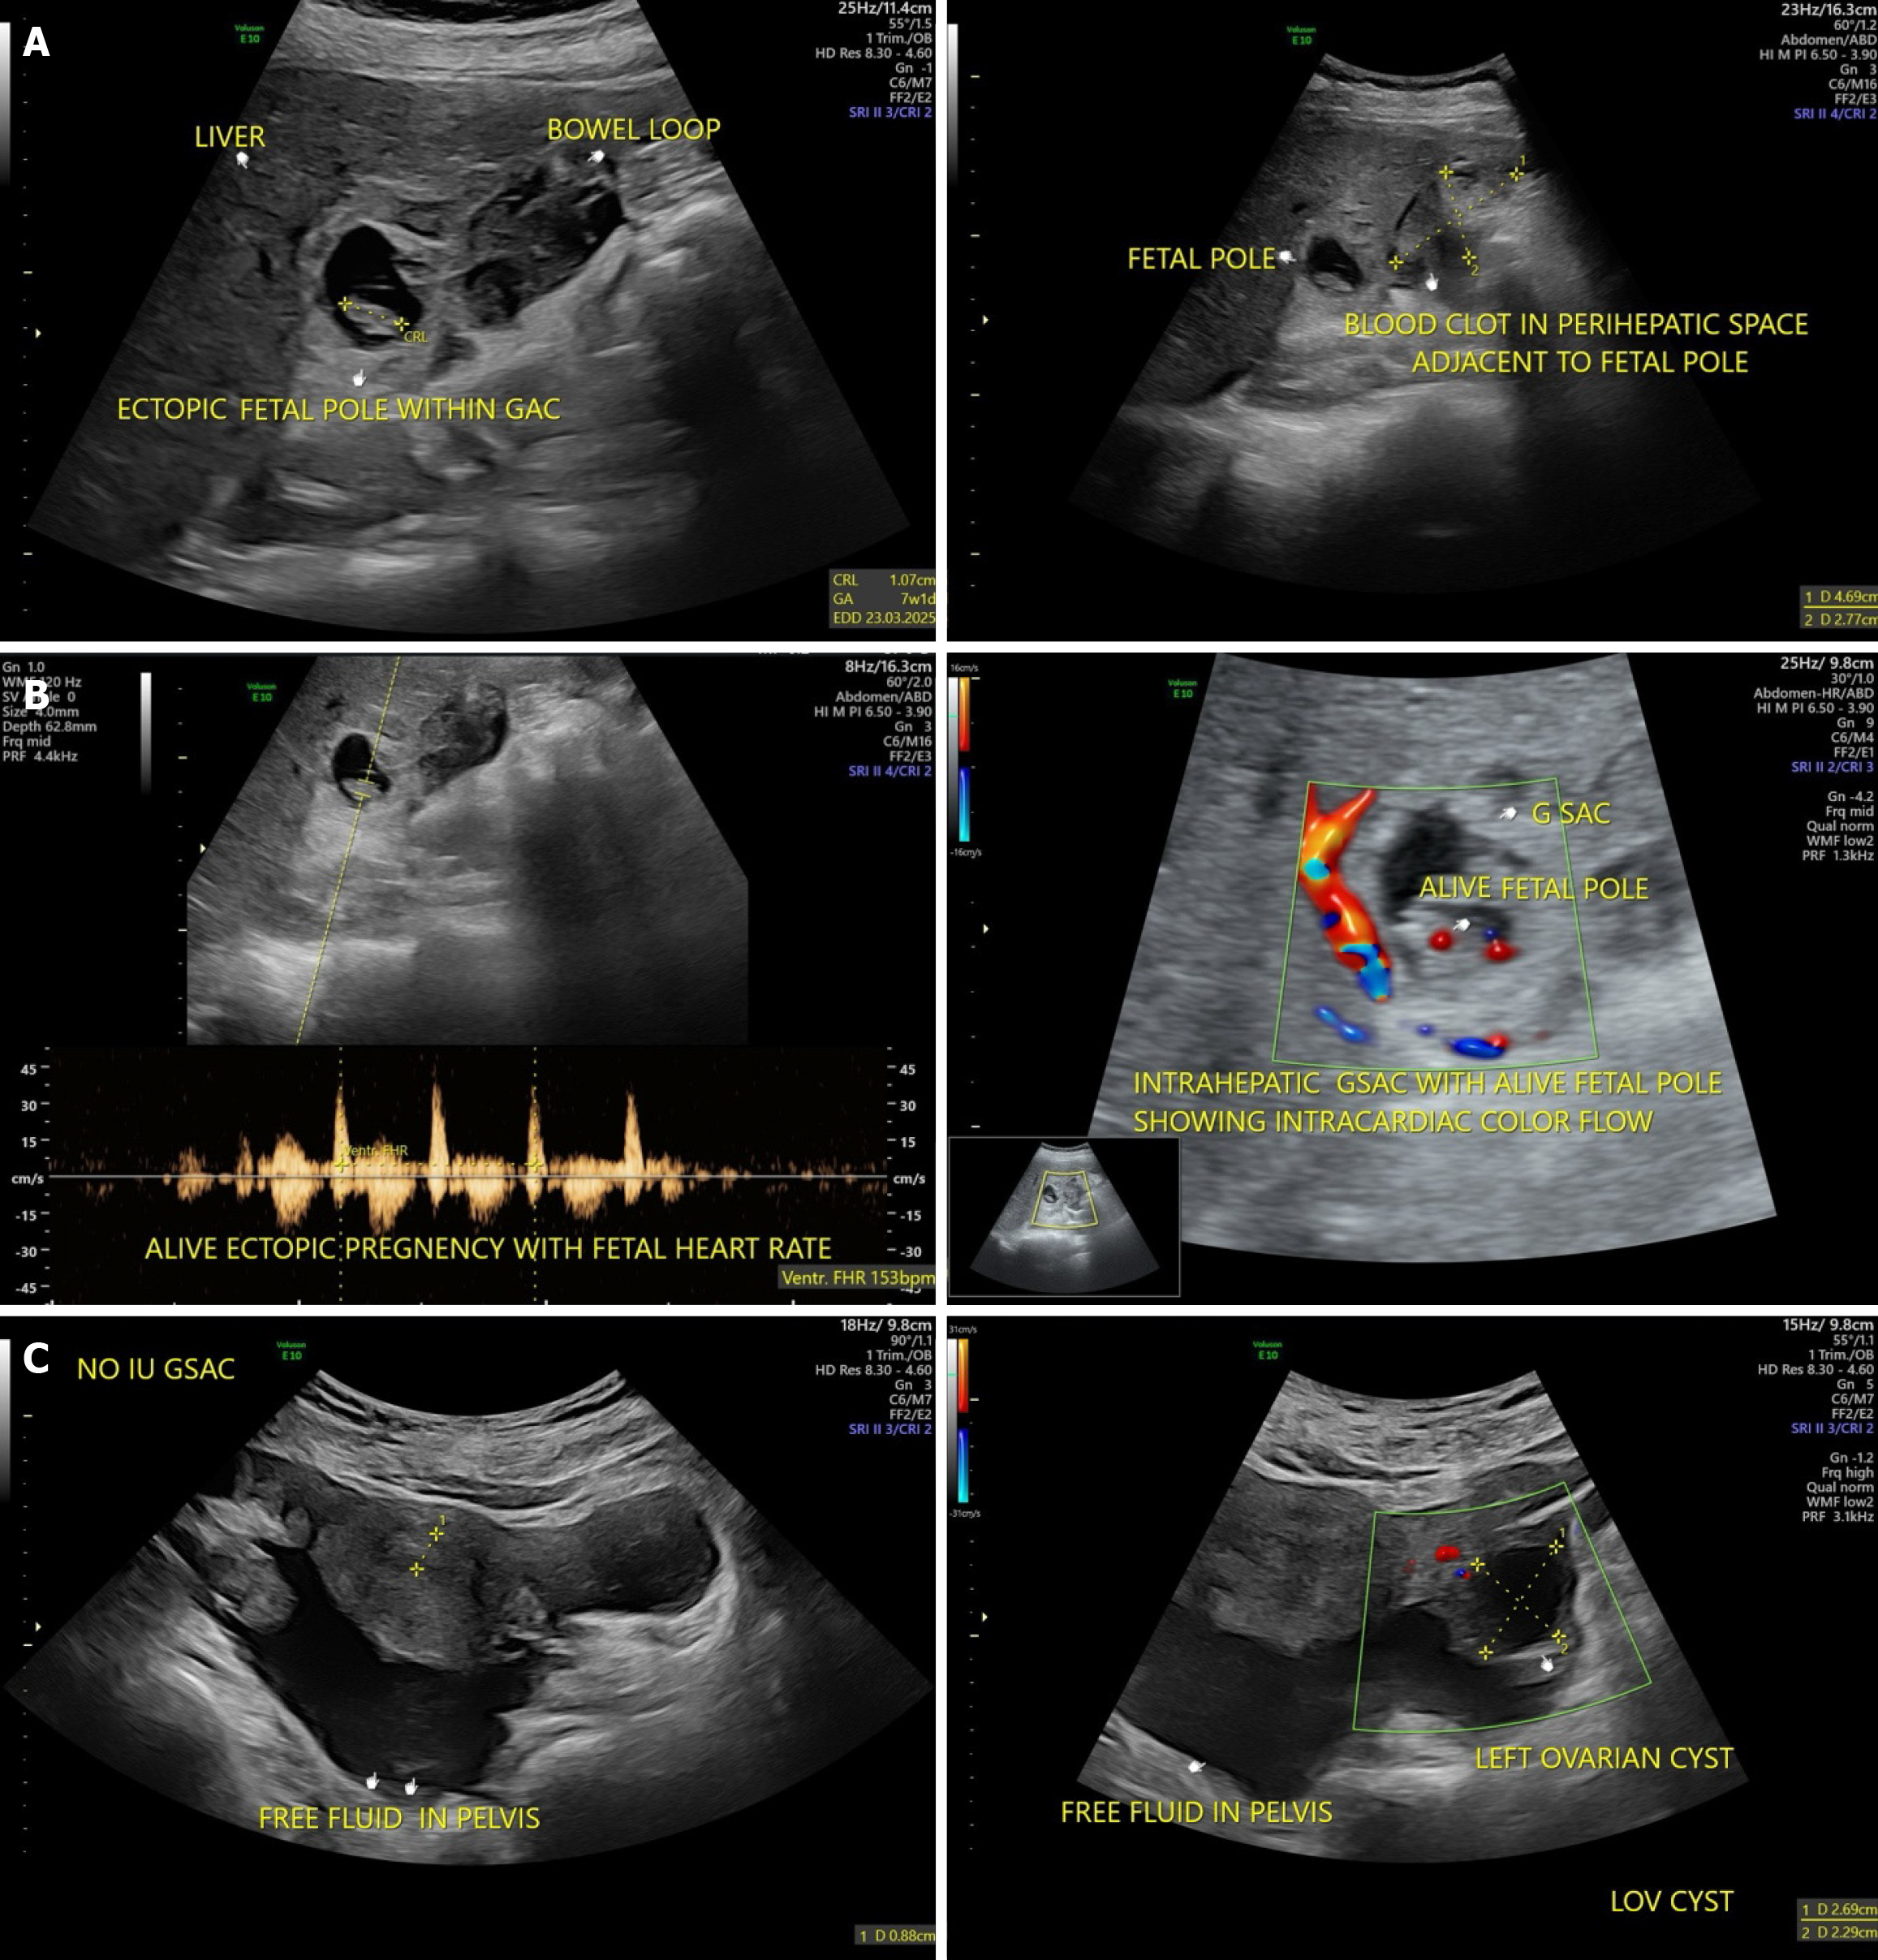

Figure 1 Abdominal ultrasound.

A: Ultrasound imaging demonstrated a large volume of free intraperitoneal fluid that was consistent with massive hemoperitoneum; B: Live ectopic pregnancy with positive fetal heart rate. Doppler study showed intracardiac color flow; C: Focused abdominal ultrasonography of the liver. Ultrasound imaging showed a heterogeneous lesion with mixed echogenicity arising from the right hepatic lobe that was suspicious of ectopic gestational implantation.